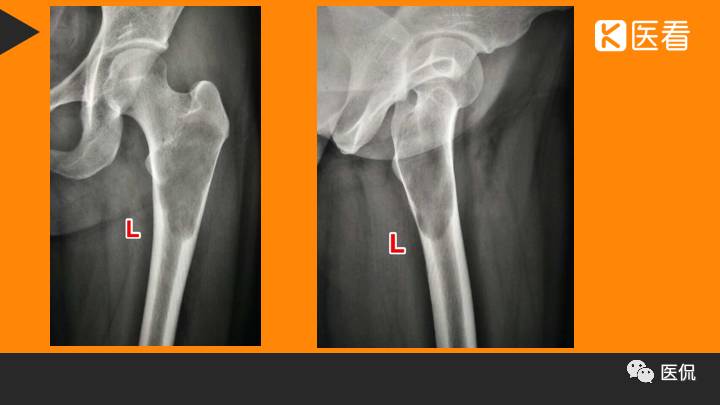

患者资料:男,26岁,左髋部疼痛10余天,无明显诱因出现左侧髋部疼痛,影像行走,夜间疼痛尤其明显。

影像资料:

(1)X线 ABC典型的表现为偏心囊状膨胀的溶骨性改变,呈单发或多房的结构,病变与正常骨的分界清楚,边缘光整,有或无硬化、皮质受压、变薄,也可吸收或破裂,突入软组织,形成局限性肿块。位于骨皮质的ABC常呈“吹出”样偏心囊胀,其外常有骨膜新骨形成的薄膜骨嵴,脊柱的ABC也表现为溶骨性膨胀性改变,病变常起始于附件向椎体发展,因此病变常偏于椎体的一侧。病变可跨过椎间关节累及到附近的椎体或肋骨。

【诊断要点】发生于青少年长骨干骺端偏心膨胀的溶骨性病变,MRI检查病灶内见有液-液平征象时应首先考虑为动脉瘤样骨囊肿。